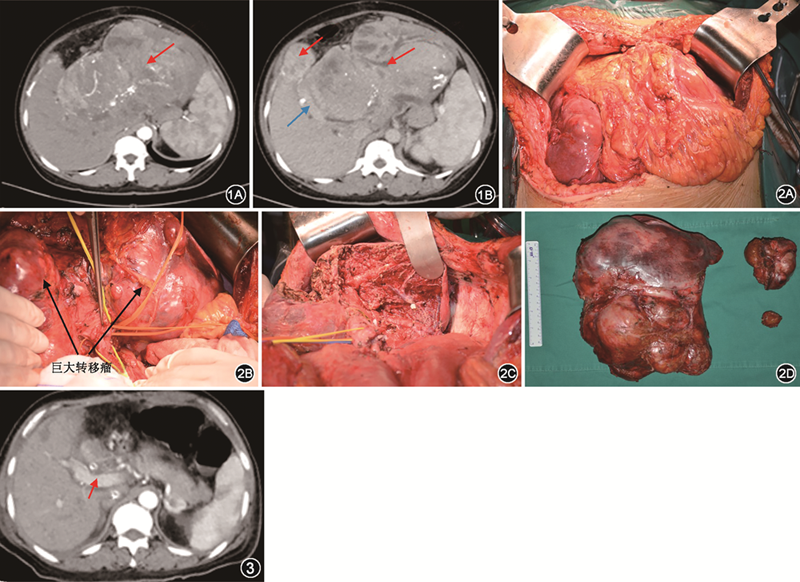

患者 女性,44岁,因“颅内孤立性纤维性肿瘤/血管外皮瘤(solitary fibrous tumors/hemangiopericytoma,SFT/HPC)术后13年,伴肺、肝、肾等多发转移5年,反复低血糖发作半年”于2019年9月22日收入清华大学附属北京清华长庚医院肝胆胰中心。患者13年前因头痛、头晕、恶心、呕吐等不适就诊于外院,诊断为右枕部颅内肿瘤,行颅内肿瘤切除术。切除标本的病理学检查结果显示,灰白色组织,大小5 cm ×5 cm×4 cm;免疫组化检查结果显示,波形蛋白(+++)、CD99(++)、EMA(-)、CD34(-);病理学诊断为右枕血管外皮细胞型脑膜瘤(Ⅱ级)。患者术后行头颅立体放疗一次。5年前复查见双肺多发转移瘤,最大者位于左肺上叶,大小约3.0 cm×5.0 cm,于外院行胸腔镜下左肺楔形切除术,术后病理学检查结果为硬化性血管瘤。患者3年前复查见肝左叶转移瘤,大小约13.0 cm×11.0 cm×9.5 cm,于外院行肝组织穿刺活检术,术后病理学检查结果为倾向转移性颅内SFT/HPC。请解放军总医院第一医学中心病理科会诊,将第一次颅内肿瘤术后病理学检查修正诊断为颅内SFT/HPC,后两次病理学检查结果均为颅内SFT/HPC转移。随后患者于外院行开腹肝左叶肿瘤切除术,术后病理学检查结果为颅内SFT/HPC肝转移。患者2年前复查见左肾转移瘤,大小约4.0 cm×5.0 cm,于外院行腔镜下左肾转移瘤切除术,术后病理学检查结果为颅内SFT/HPC肾转移。患者半年前出现反复发作的低血糖,CT检查结果示肝脏巨大转移瘤,左肾和肺多发转移瘤,分别于2019年4月、2019年5月、2019年7月于外院行肝动脉+膈动脉化疗栓塞术,前两次使用多柔比星+碘化油,后一次使用博来霉素+碘化油。治疗后肝左叶肿瘤最大径由原来的约17 cm增至约25 cm,且每次介入治疗后血糖仅可维持正常水平3~5 d,然后再次出现反复发作的低血糖,发作频率逐渐增至约3.5 h发作一次,发作时血糖低至1 mmol/L,时有昏迷,夜间需进食2~3次。患者入院前一般情况尚可,小便正常,无其他慢性病史。入院体检:心率123 次/min,体温、呼吸、血压等正常。腹部外形膨隆,反L形手术切口愈合好,上腹部可触及巨大肿块,约达剑突下20 cm,边界不清,固定,质地硬,表面不光滑。血糖化血红蛋白、空腹胰岛素均低于正常值范围。腹部CT平扫见肝内多发大小不等肿块影,左肝为著,最大径约24.2 cm×13.3 cm,内见多发斑片状阴影及结节影;腹部CT增强扫描见实性部分强化,分别由肝动脉及膈动脉分支供血。门静脉增粗,最宽处约24 mm,门静脉左支及分支显示不清(图1)。左肾和双肺也可见多发肿块影,最大径约5 cm,密度不均匀,增强扫描可见不均匀强化。完善相关术前准备,患者和家属签署手术同意书后行手术治疗,术中见肿瘤位于左肝及部分肝脏右前叶,大小约25 cm×20 cm×15 cm,肝脏6段腹侧和背侧各见一个肿瘤,大小分别为7.0 cm×6.6 cm×6.0 cm和3.0 cm×3.0 cm×1.5 cm。肿瘤质韧,表面光滑,呈大结节样改变。肿瘤活动度极差,占位效应明显,游离困难(图2)。行扩大左半肝切除术,手术时间约17 h,出血量约10 000 ml,静脉滴注红细胞20 U、血浆3 200 ml,术中血压维持困难,需大量升压药维持。患者术后出现发热,体温最高达39 ℃,血常规检查示白细胞计数最高达32.85×109/L,中性粒细胞占比91%,痰液培养出白色念珠菌,给予亚胺培南、利奈唑胺和氟康唑等多种抗菌药物治疗后好转。患者术后清醒后出现反复发作的抽搐和对答不正确,头颅增强MRI检查结果见脑内多发异常强化灶,考虑转移。请神经内科和神经外科会诊后,给予左乙拉西坦片后患者病情好转。患者术后复查腹部增强CT,肝内未见肿瘤残余,门静脉右支内径正常,无受压及血栓形成(图3)。患者术后未再出现低血糖发作,术后第19天出院。

切除标本肉眼可见紧邻肝脏切缘和肝门断端有一个巨大肿瘤,大小约24 cm×19 cm×11 cm,肿瘤切面颜色为灰黄、灰粉和灰褐色,大部分呈鱼肉状,质软,局部有囊腔,直径0.1~4.0 cm,内有血凝块,部分囊腔内可见灰黄色胶冻样物。肿瘤周围可见2个卫星灶,大小分别为1.4 cm×1.4 cm×0.5 cm和1.4 cm×0.8 cm×0.8 cm。肝脏6段腹侧和背侧肿瘤大小分别约7.0 cm×6.6 cm×6.0 cm和3.0 cm×3.0 cm×1.5 cm,剖开后肉眼观同前。镜下描述:肝肿瘤细胞呈短梭形,核分裂象2个/10个高倍视野,大小一致,细胞密集,无特定排列,其中可见大量裂隙样血管,内衬扁平内皮细胞,部分血管分支呈鹿角状,部分区域囊性变,局部可见出血及大片坏死,纤维组织增生。未见明确脉管内瘤栓及神经侵犯,未累及肝脏切缘、肝门区及肝被膜。免疫组化结果提示,波形蛋白、CD34、CD31、STAT6均为阳性,凝血因子